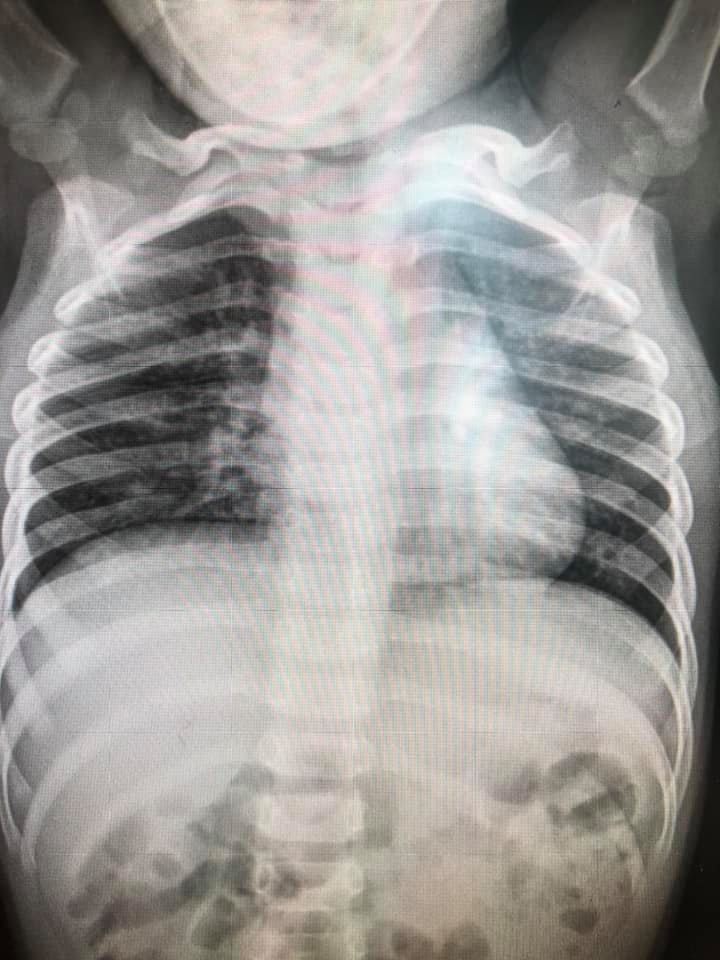

เผยภาพปอดเด็กป่วย RSV ชี้ ไม่มีวัคซีน ไม่มียา ต้องรักษาตามอาการ แนะวิธีป้องกัน งดจูบ หอม สวมหน้ากากอนามัย งดไปแหล่งคนเยอะ ทำความสะอาดของเล่น

1. มาด้วยอาการ ไข้ ไอ เสมหะ หอบเหนื่อย มีอาการน้อยถึงรุนแรง

2. มักพบในเด็กอายุน้อยกว่า 5 ปี ยิ่งอายุน้อยยิ่งรุนแรง กลุ่มเสี่ยง คือ อายุน้อย มีโรคประจำตัวปอดหรือหัวใจ คลอดก่อนกำหนด

7. การพยากรณ์โรค : ปอดบวม ปอดอักเสบ ใช้เวลารักษา 3-7 วันกรณีไม่รุนแรง ถ้ารุนแรงอาจใช้เวลา 10-21 วัน

ภาพจาก เฟซบุ๊ก Infectious ง่ายนิดเดียว